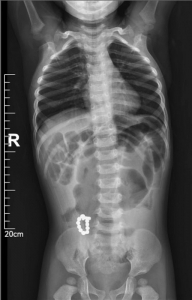

1.患儿:李某某,性别:男,年龄:2岁;简要病史:2岁男孩,因间断腹痛5天,发现消化道异物1天入院。5天前患儿无明显诱因出现腹痛,家长未予特殊重视,1天前患儿出现呕吐伴便秘,就诊于当地医院,行腹部X线片提示消化道异物(磁力球?),遂急诊就诊于我院,诊断“消化道异物(磁力球?)”收住我科。发病后患儿精神食欲差,予以开塞露后排大便1次,小便正常。既往身体健康,无家族遗传病史,心肺腹查体无异常。初步诊断:消化道异物(磁力球?)接下来,患儿需要做什么检查呢?是继续观察自行排出?还是内镜下取出?又或是剖腹探查取出呢?完善腹部X片 (两次间隔时间6小时)显示:磁力球位置未见明显变化(如下图),拟行手术治疗,手术方式为:剖腹探查术。手术探查示 (如下图):胃大弯处可见有2处直径约0.5cm穿孔 (穿孔内取出磁力球5颗),距屈氏韧带约40cm肠管近系膜侧可见2处直径约0.5cm穿孔 (穿孔内取出磁力球10颗),抗菌薇乔全层间断缝合一层胃大弯及小肠肠管穿孔,间断浆肌层加固一层;查无漏气漏液现象,吻合口直径通过顺畅。术毕。术后治疗:予以抗感染、肠外营养、过渡饮食对症治疗,患儿恢复顺利,康复出院。2.患儿:贾某某,性别:男,年龄:1岁10个月;简要病史:1岁10个月男孩,因精神反应欠佳伴烦躁哭闹4天入院。患儿于入院近4天精神反应欠佳,烦躁、哭闹,手捂腹部,呕吐2次,就诊于卫生所予以腹部外敷药物治疗,效果欠佳,后就诊于妇幼保健院,行腹部X片检查,提示消化道异物,自发病以来精神可,食欲欠佳,大便1次,小便量少。既往身体健康,无家族遗传病史,心肺腹查体无异常。初步诊断:消化道异物(磁力球?)完善腹部X片(两次间隔时间6小时)显示:磁力球位置未见明显变化(如下图),拟行手术治疗,手术方式为:剖腹探查术。手术探查示(如下图):距屈氏韧带约30cm小肠有2处直径约0.5cm穿孔(穿孔内取出磁力球1颗、螺丝1颗),距肛门口20cm处乙状结肠近系膜侧可见2处直径约0.5cm穿孔 (穿孔内取出磁力球9颗),据回盲部40cm处小肠系膜可见2处直径约0.5cm穿孔。术后治疗:予以抗感染、肠外营养、过渡饮食对症治疗,患儿恢复顺利,康复出院。